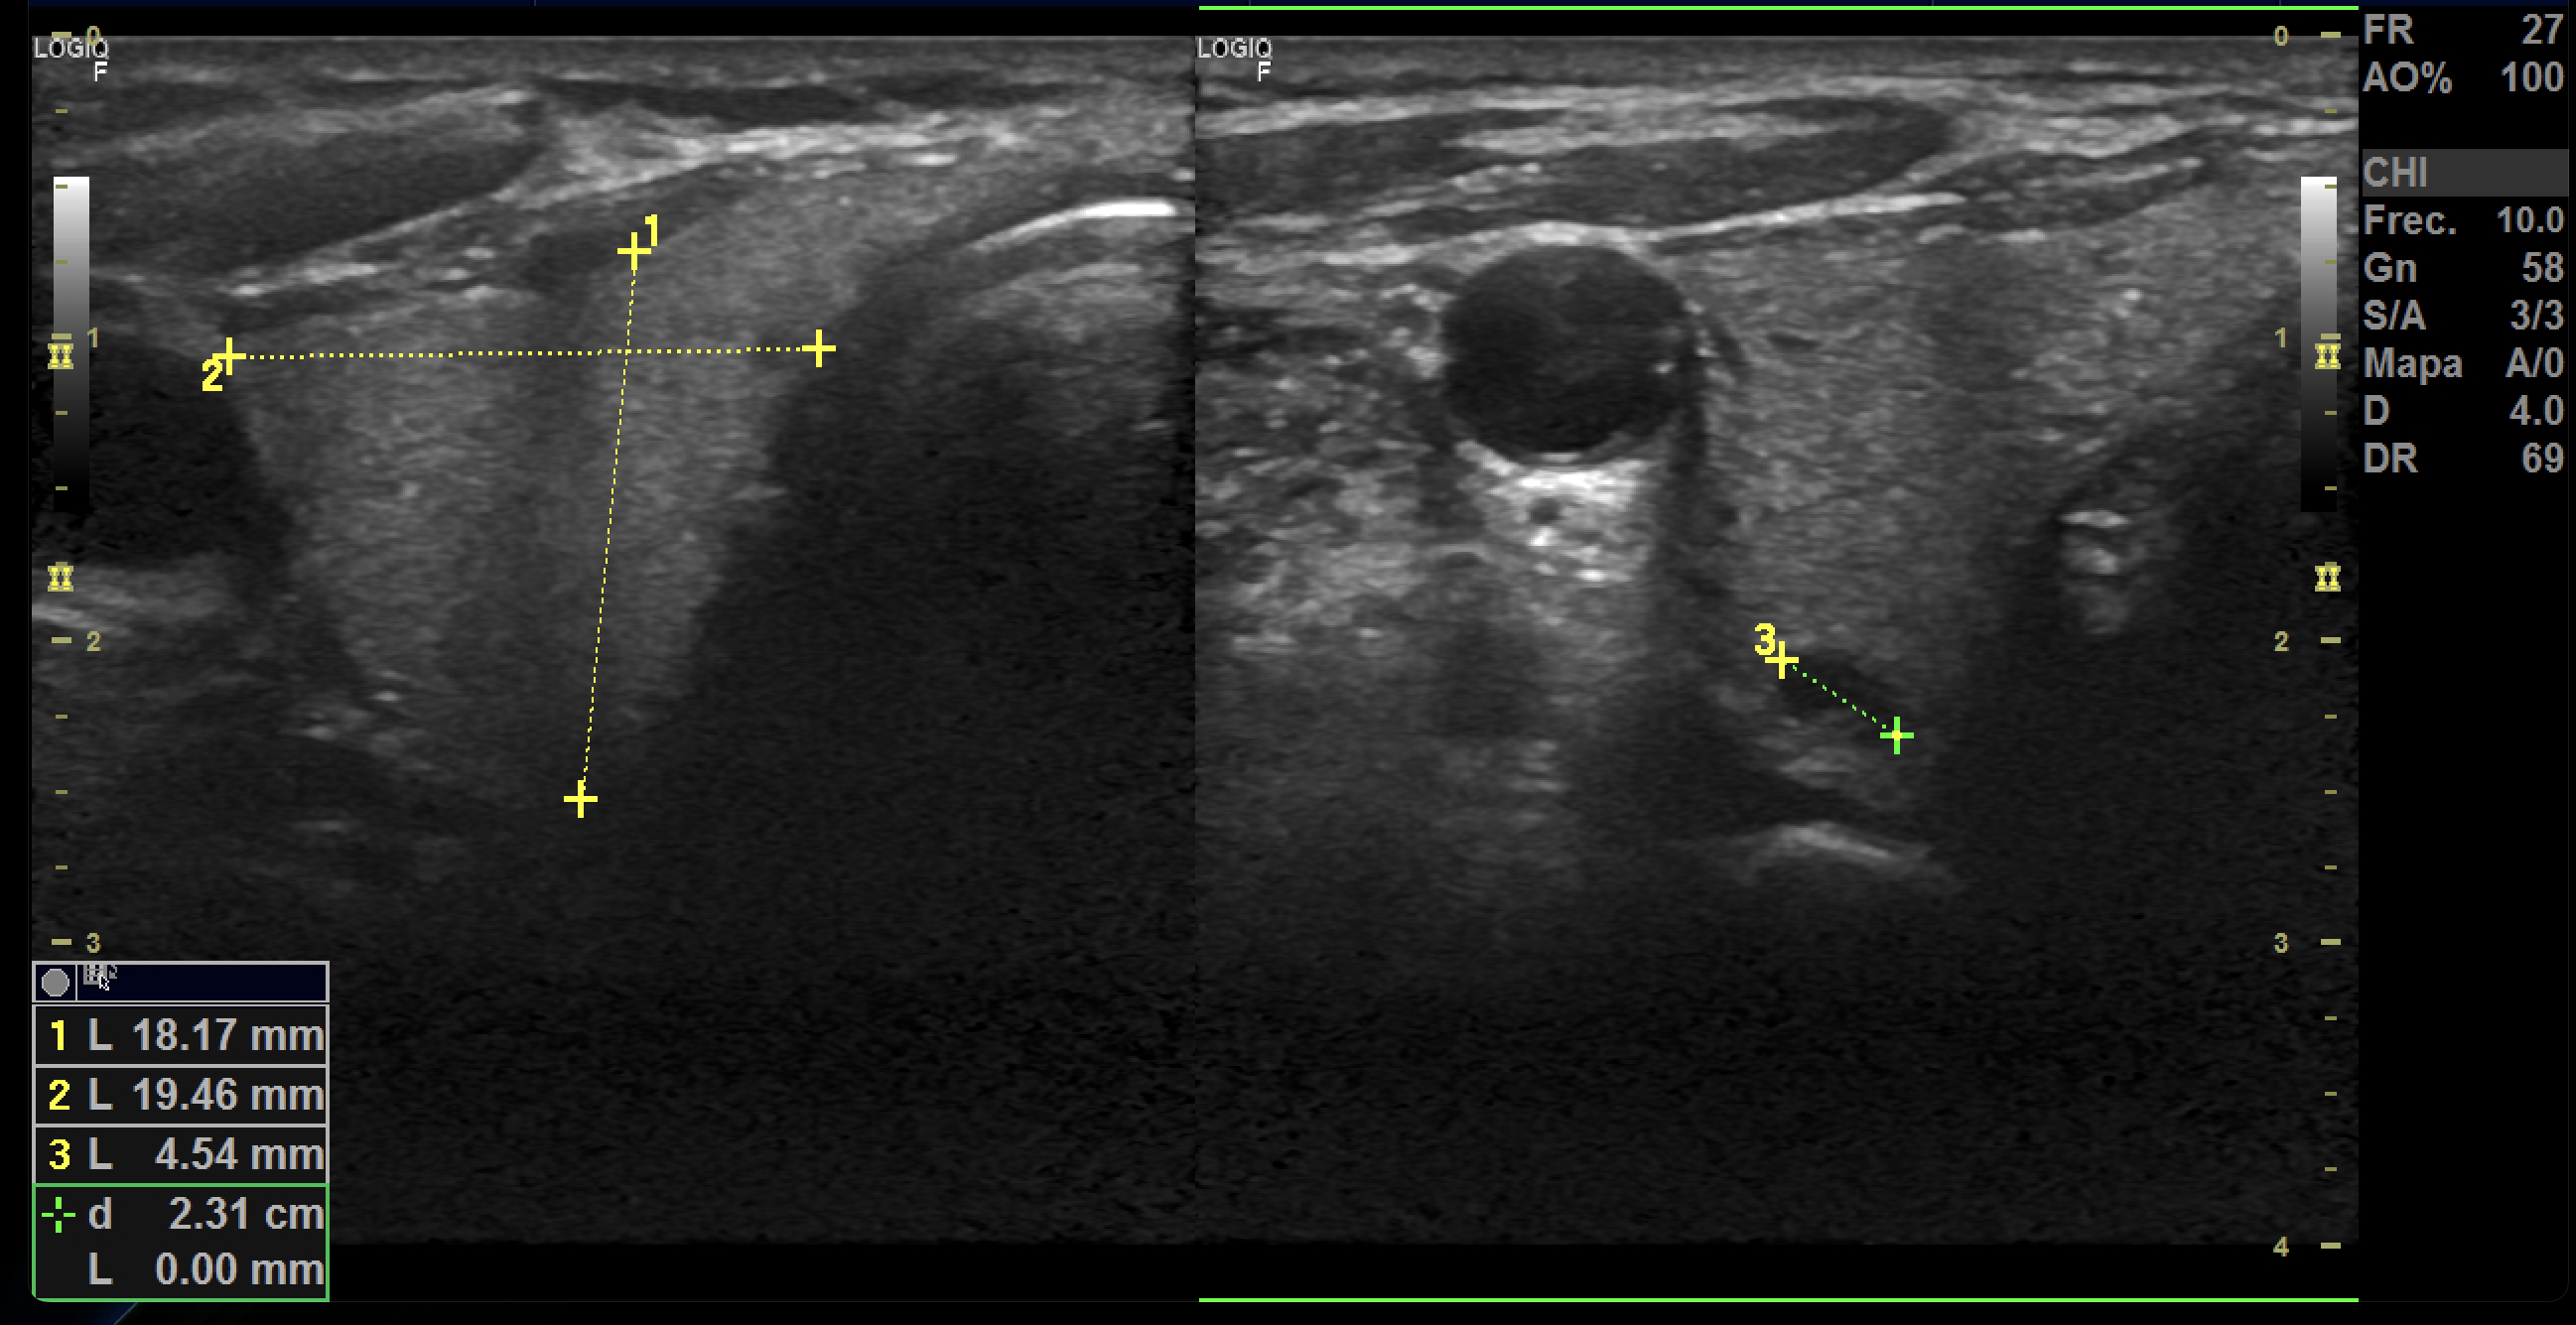

Hallazgos ecográficos

La ecografía Doppler carotídea realizada en AP mostró placas hiperecoicas y calcificadas en ambas carótidas comunes, con estenosis bilateral de aproximadamente 20% del lumen. Carótidas externas e internas permeables y morfología normal.